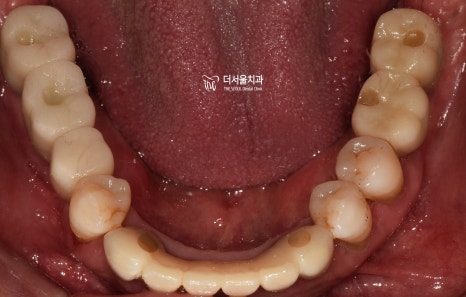

바로 사진부터 보여드리겠습니다.

평소에 구강 관리를 하지 않아서

치태와 치석이 잔–뜩 쌓여 있었고

잇몸이 새빨갛게 부었으며

앞니/어금니 할 것 없이 흔들림을 보였습니다.

아래 사진을 보면

1. 잇몸치료로

치석과 치태를 말끔히 제거했으며

2. 픽스쳐 식립으로

어금니의 기능을 회복시킬 수 있었습니다.